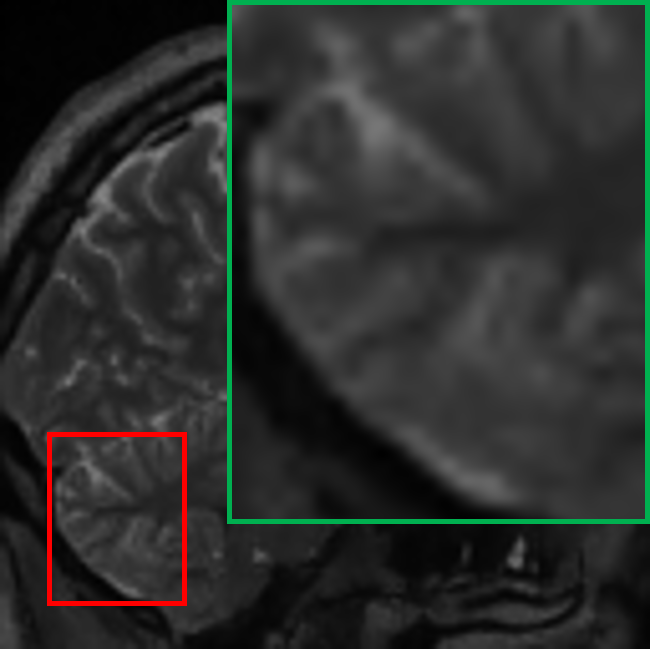

TABLE VII: Clinical evaluation for MS case

Real 3T MRI Real 7T MRI 7T-like SR MRI (3T to 7T)

[Uncaptioned image] [Uncaptioned image] [Uncaptioned image]

In another case involving a patient with multiple sclerosis (MS), characterized by periventricular and subcortical white matter abnormalities. MS lesions, often appearing as small “dark holes” in the brain on T1w MRI, are notoriously difficult to identify on lower-field MRIs. As shown in Table VII, the real 7T MRI provided a significant improvement in resolution compared to the 3T MRI, enabling clearer visualization of MS-related changes in the periventricular regions, which highlights the importance of 7T MRI in detecting subtle lesions. By applying our student model to super-resolve the 3T MRI into a 7T-like quality, the resulting SR image closely matched the real 7T MRI, markedly improving the depiction of the periventricular white matter, making the small “dark holes” indicative of MS lesions much more apparent.